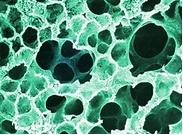

呈孤立的圓形肺炎變的肺炎謂球形肺炎(spherical pneumonia),是一個以X線胸片的形態表現特點而命名的肺炎。

球形肺炎,球形肺炎癥狀,球形肺炎治療